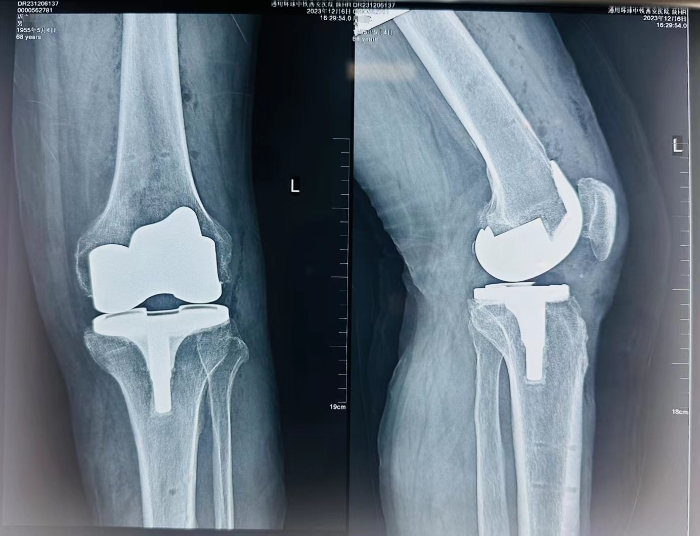

在手麻科(kē)的配合下,手術(shù)順利完成,機(jī)器人(rén)輔助下的截骨操作(zuò)和假體(tǐ)植入都(dōu)實現了毫米的精度,爲延長假體(tǐ)的使用壽命提供了有效的技術(shù)基礎。術(shù)中出血量少,術(shù)後傷口美容縫合護理(lǐ)無管化,術(shù)後4小時周叔即可(kě)進行康複訓練,包括主動和被動活動、行走練習等。

術(shù)後